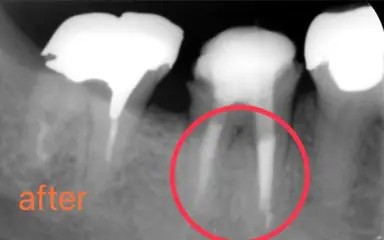

初診時の口腔内写真です。他院での根管治療の際にリーマーが折れ、歯の中に残ってしまっている症例です。

レントゲン写真をご覧ください。この直線的に写っている怪しい影が破折リーマーです。